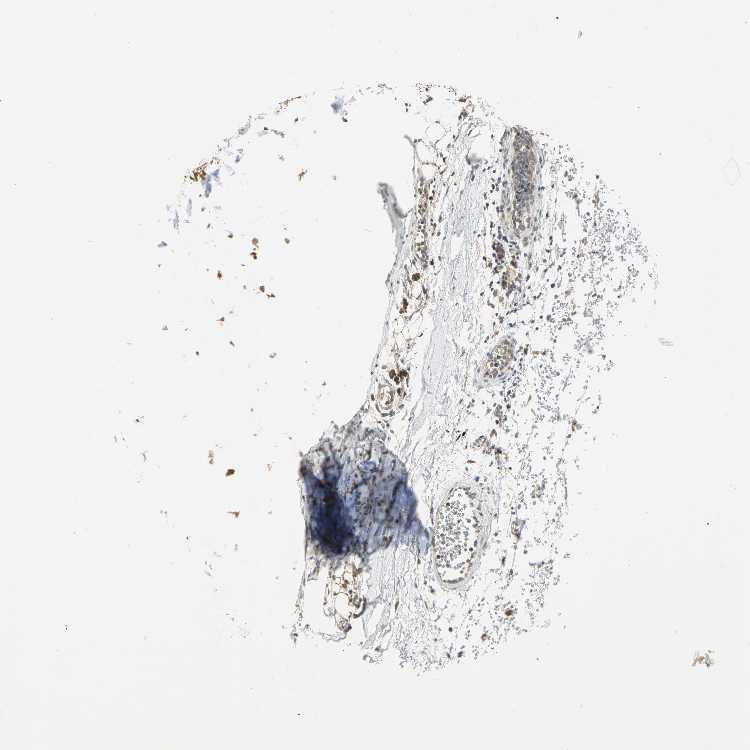

ADIPOSE TISSUE - Antibody stainingi

Antibody staining in the annotated cell types in the current human tissue is reported as not detected, low, medium, or high, based on conventional immunohistochemistry profiling in selected tissues. This score is based on the combination of the staining intensity and fraction of stained cells.

Each image is clickable and will lead to virtual microscopy that enables deeper exploration of all samples and also displays staining intensity scores, fraction scores and subcellular localization as well as patient and tissue information for each sample.

Antibody HPA041785Antibody HPA069311Antibody CAB005580

Adipocytes LowHighNot detected